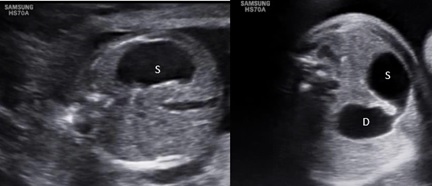

Tuy nhiên các dấu hiệu này có thể xuất hiện muộn, cuối quí 2 hay đầu quí 3. Vì vậy, một số trường hợp tắc tá tràng nhưng siêu âm giữa quí 2 (18-21 tuần) chưa xuất hiện đa ối và hình ảnh bóng đôi chưa rõ. Dấu hiện duy nhất có thể gặp là hình ảnh dạ dày dãn lớn với môn vị rất rõ. Các trường hợp này cần siêu âm lập lại và hình ảnh bóng đôi sẽ rõ ở lần khám sau.

Hình 2: Siêu âm lúc 18 tuần có hình ảnh dạ dày (S) dãn lớn, siêu âm kiểm tra lại 2 tuần sau có hình ảnh bóng đôi thông nhau của dạ dày (S) và tá tràng (D)